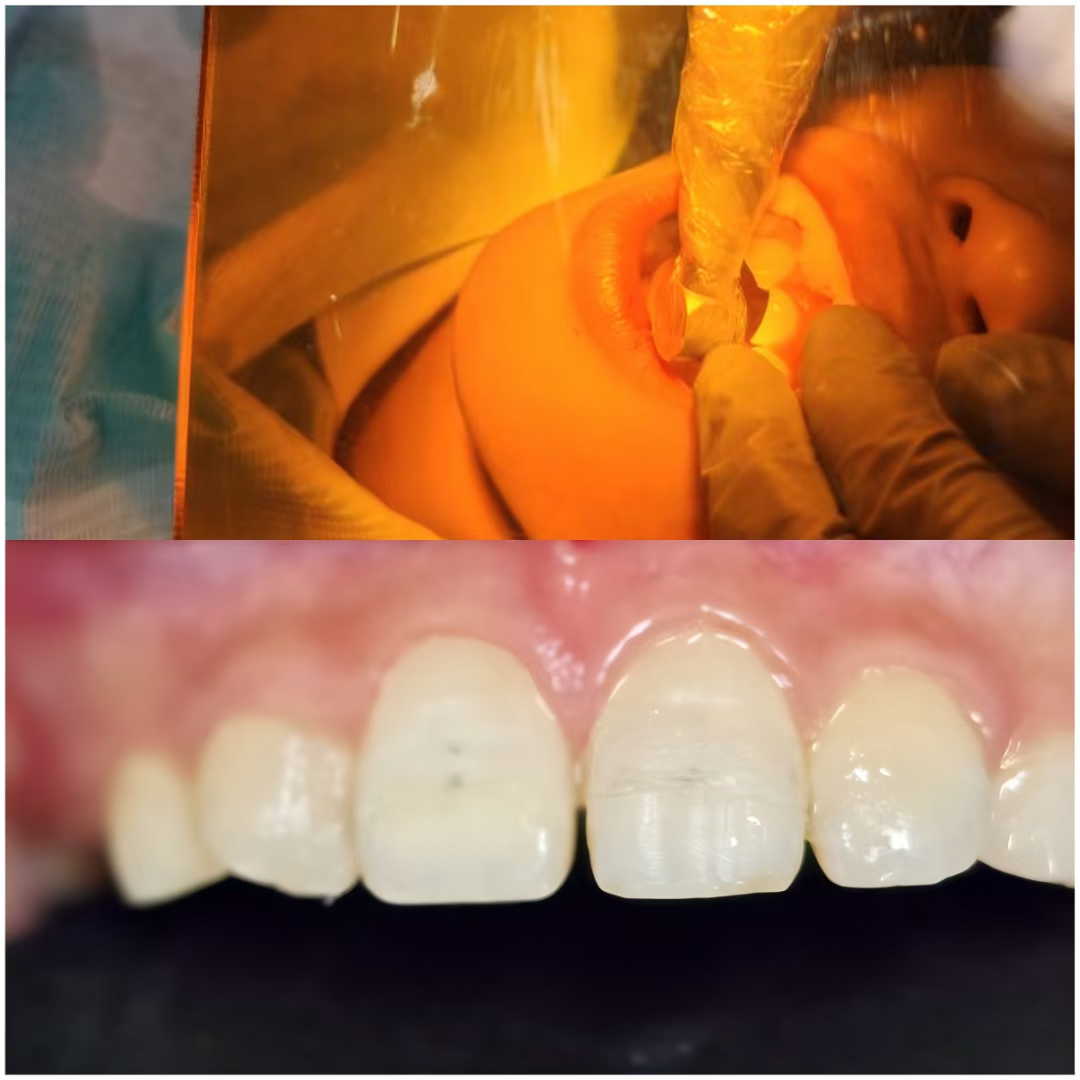

10岁的小朋友,在小区玩滑板时不慎摔倒,磕到上颌门牙,哭着被家长紧急送诊。慌乱中家长想起“断牙泡牛奶”的知识,将脱落牙体浸泡在牛奶中后送至我院口腔科。经口腔科团队合作,尽快为患儿实施“断牙体树脂粘接术”——将清洁后的原牙体精准复位,用专用树脂粘接固定,同时对颊侧缺损处做渗透树脂修复,还原牙冠自然形态。术后患儿门牙外形立刻恢复整齐,哭闹情绪当场缓解,当天就能正常吃软的食物。

修复前:

修复后: